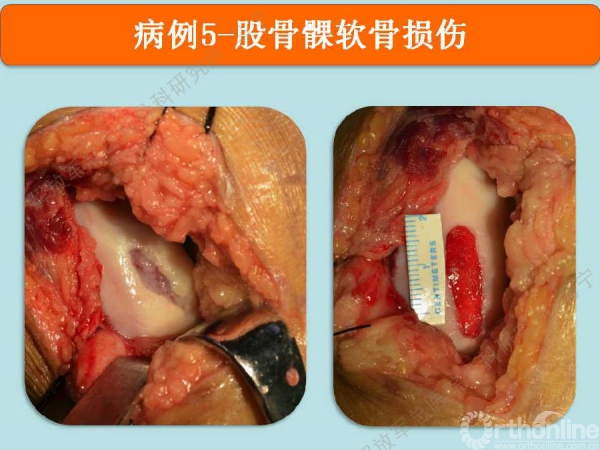

病例5

陈某,男,31岁,足球训练伤。

术中显示损伤部位及第四代组织工程软骨修补术后。术后三个月核磁显示组织工程软骨具备一定厚度,胶原含水量接近正常,还存在GAP现象。随访还在进行中。